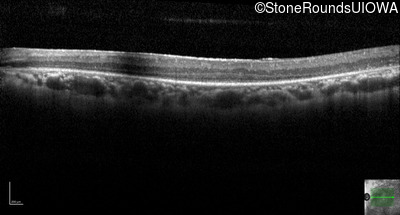

Age at visit: 62 years

OD OS

This 62 year old man had poor night vision as a teenager and developed difficulty with his peripheral vision in his early forties. His parents both grew up in the small village in Taiwan.

Diagnosis & molecular findings

Disease Gene Allele 1 variant(s) Allele 2 variant(s) Inheritance mode

AR Retinitis Pigmentosa EYS Cys2139Tyr TGT>TAT Cys2139Tyr TGT>TAT AR